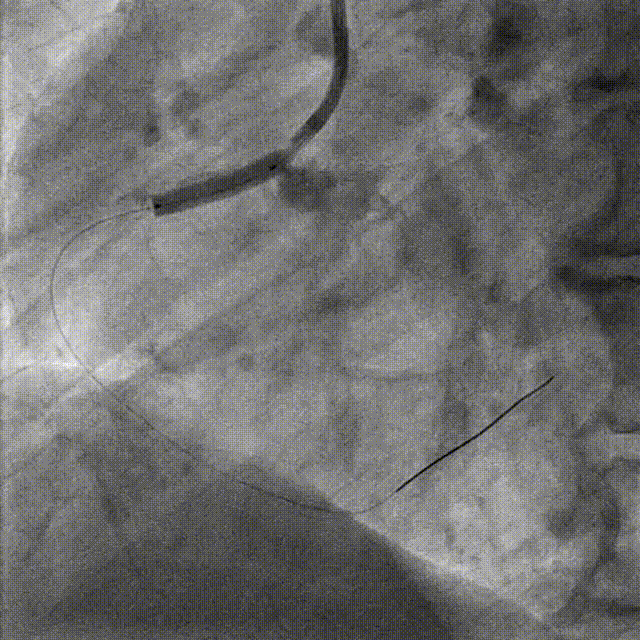

Lesion preparation NC 2.5*12mm → Cutting balloon 4.0*10mm @ 12atm

Angiography & DCB Angioplasty DCB 4.0*20mm @ 8atm, 60s

DES Deployment & Optimization DES 4.0*20mm → NC 4.0*12mm @ 20atm